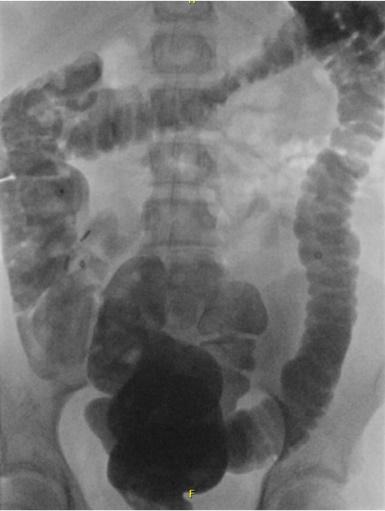

- Röntgenfoto van de buik: Hiermee kan worden bekeken hoe ernstig de verstopping is. Soms wordt dit gecombineerd met een markerstudie, waarbij uw kind capsules inneemt om de snelheid van de ontlasting te meten.

Coloninloop: Dit is een onderzoek waarbij contrastvloeistof via het poepgat wordt ingebracht om de dikke darm beter te bekijken. Daarna worden er een aantal röntgenfoto's na elkaar gemaakt, zodat de darm goed te zien is. Zo kan de arts goed beoordelen of de darm lang, wijd of kronkelig is.- Als uw kind dit spannend vindt, kan een medisch pedagogisch zorgverlener u en uw kind helpen om ervoor te zorgen dat dit proces zo soepel mogelijk verloopt.

- Coloninloop: Onderzoek waarin de dikke darm zichtbaar wordt gemaakt met vloeistof en rontgenfoto’s.